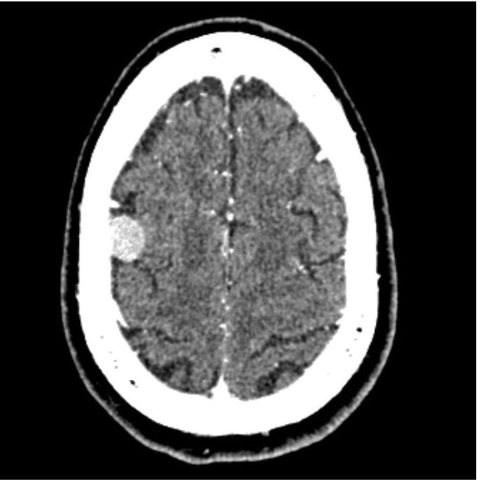

Looking at the axial CT images carefully, you see mass which has taken up the contrast and appears bright. Which of these cerebral cortical regions does this mass overlie?

Prefrontal cortex

Auditory cortex

Primary motor cortex

Visual cortex